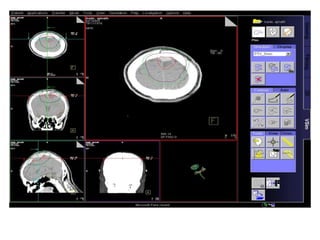

RT planning: meningioma

GTV/CTV = residual tumour / tumour bed for gr II / gr III

CTV = 5 mm for benign meningiomas

2 - 3 cms for high grade meningiomas / HPC

PTV = 2mm for SRT

5mm for 3DCRT

All normal structures contoured

Dosage:

Gr-I:

54Gy/30# conformal RT

25Gy/5# / 13Gy/1#

Gr II & III meningioma:

60Gy/30#/6wks

Conformal RT

Grade I Grade II/III

Tharmoplastic mask

CT scan with contrast- 3 mm slice

MRI scan with T1 contrast & T2 flair is a must

RT planning: meningioma GTV/CTV= residual tumour / tumour bed for gr II / gr III CTV = 5 mm for benign meningiomas 2 - 3 cms for high grade meningiomas / HPC PTV = 2mm for SRT 5mm for 3DCRT All normal structures contoured Dosage: Gr-I: 54Gy/30# conformal RT 25Gy/5# / 13Gy/1# Gr II & III meningioma: 60Gy/30#/6wks Conformal RT Grade I Grade II/III Tharmoplastic mask CT scan with contrast- 3 mm slice MRI scan with T1 contrast & T2 flair is a must